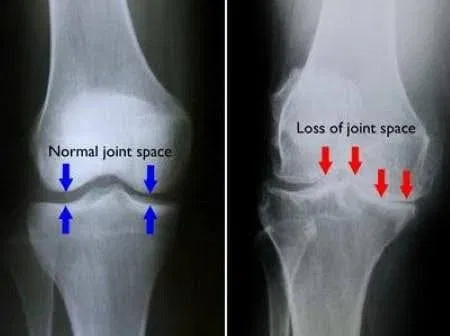

An MRI scan is the gold standard for visualising soft tissue structures including the meniscus, and can confirm the location, type, and severity of a tear. A weight-bearing x-ray may also be helpful to rule out bony involvement or assess for arthritic changes.

Hyaluronic acid injections to improve joint lubrication and reduce pain in those where articular cartilage changes or patellofemoral joint degeneration accompany the running injury.